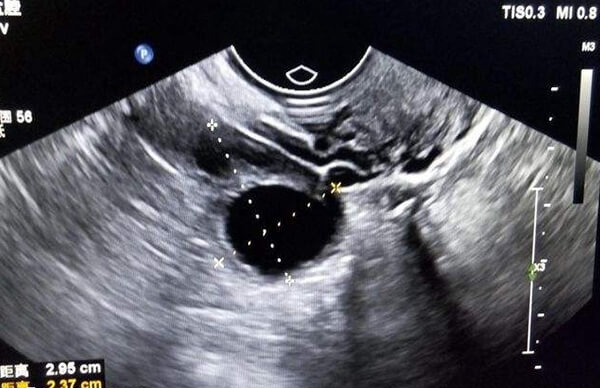

3、排卵监测

人工授精周期开始后,医生会根据月经周期和排卵情况安排就诊时间,并开始通过b超监测卵泡发育。在这个过程中,部分患者会根据卵泡发育情况使用促排卵药物。